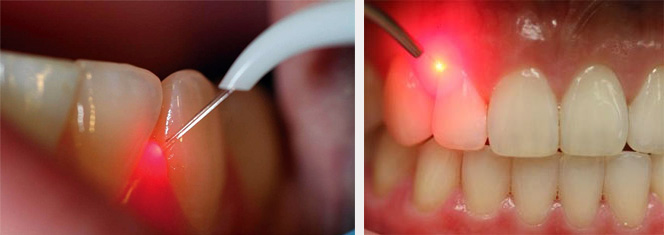

Лазерный кюретаж или антибактериальная фотодинамическая терапия (ФДТ) в странах Европы успешно применяется для лечения пародонтита уже более 15 лет. В результате лечения методом ФДТ любых форм хронического пародонтита достигается стабильный продолжительный эффект.

Лечение пародонтита методом ФДТ происходит по простой схеме:

Огромным преимуществом использования данного метода лечения пародонтита является то, что разрушается только патогенная флора, на здоровые ткани лазер и фотосенсибилизатор никакого влияния не оказывают. В результате антибактериальной фотодинамической терапии пораженные участки периодонта обретают защиту в виде фотокоагуляционной пленки, которая не допускает попадания бактерий и способствует скорейшему закрытию зубодесневых карманов.